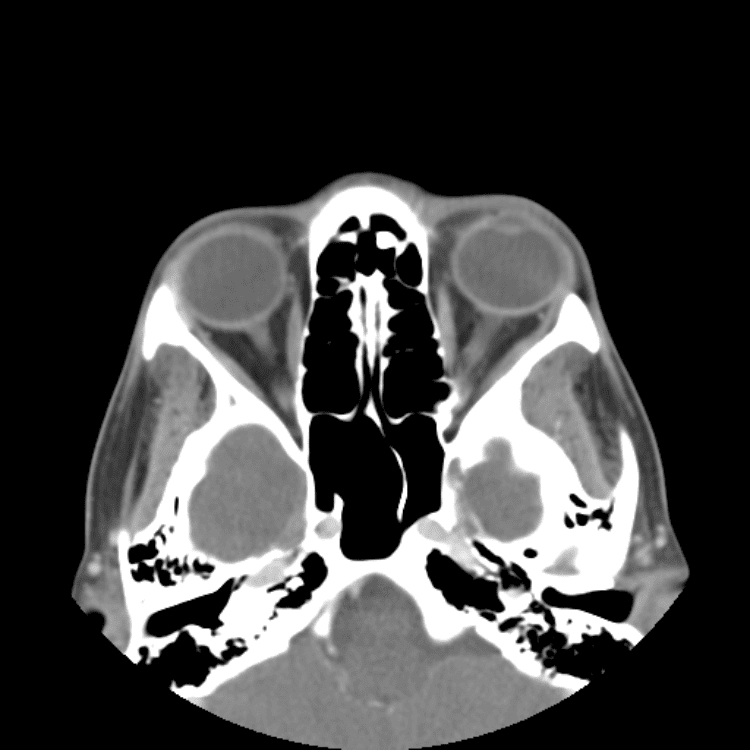

Head and Neck

Practice

Simulates call by including subtle or difficult cases and some normals.

27 cases